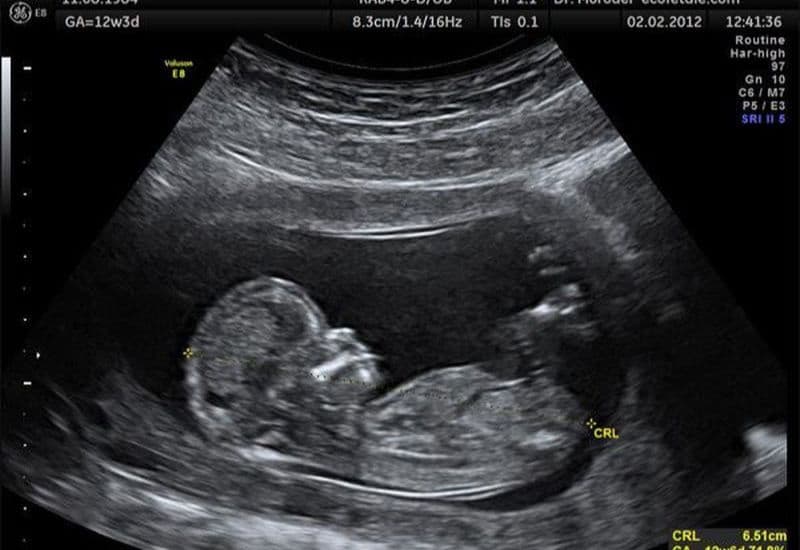

Xương mũi thai nhi thường bắt đầu hình thành rõ nét vào tuần thứ 12 của thai kỳ. Việc siêu âm đo chiều dài xương mũi thai nhi theo tuần giúp bác sĩ chẩn đoán hình ảnh và theo dõi sự phát triển tổng thể của bé.

Để biết bé có đang phát triển khỏe mạnh hay không, các bác sĩ sẽ đối chiếu kết quả đo siêu âm với các chỉ số tiêu chuẩn. Dưới đây là bảng chiều dài xương mũi thai nhi tham khảo theo từng tuần tuổi: